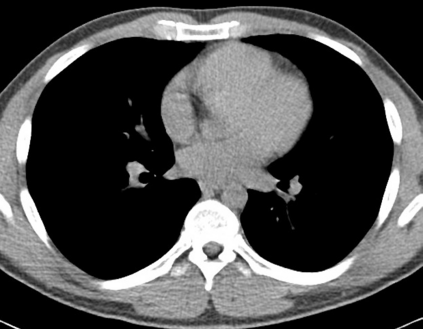

We propose a novel continual self-supervised learning (CSSL) framework for simultaneously learning diverse features from multi-window-obtained chest computed tomography (CT) images and ensuring data privacy. Achieving a robust and highly generalizable model in medical image diagnosis is challenging, mainly because of issues, such as the scarcity of large-scale, accurately annotated datasets and domain shifts inherent to dynamic healthcare environments. Specifically, in chest CT, these domain shifts often arise from differences in window settings, which are optimized for distinct clinical purposes. Previous CSSL frameworks often mitigated domain shift by reusing past data, a typically impractical approach owing to privacy constraints. Our approach addresses these challenges by effectively capturing the relationship between previously learned knowledge and new information across different training stages through continual pretraining on unlabeled images. Specifically, by incorporating a latent replay-based mechanism into CSSL, our method mitigates catastrophic forgetting due to domain shifts during continual pretraining while ensuring data privacy. Additionally, we introduce a feature distillation technique that integrates Wasserstein distance-based knowledge distillation (WKD) and batch-knowledge ensemble (BKE), enhancing the ability of the model to learn meaningful, domain-shift-robust representations. Finally, we validate our approach using chest CT images obtained across two different window settings, demonstrating superior performance compared with other approaches.